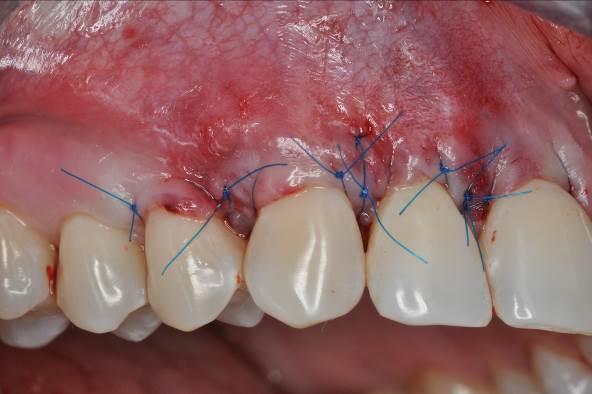

05/06 - Complete coverage of the mucoderm® matrix and tension-free flap closure.Multiple gingival recessions treated with the modified coronally advanced flap in conjunction with mucoderm® and Straumann® Emdogain® - Dr. D. B. Hangyási